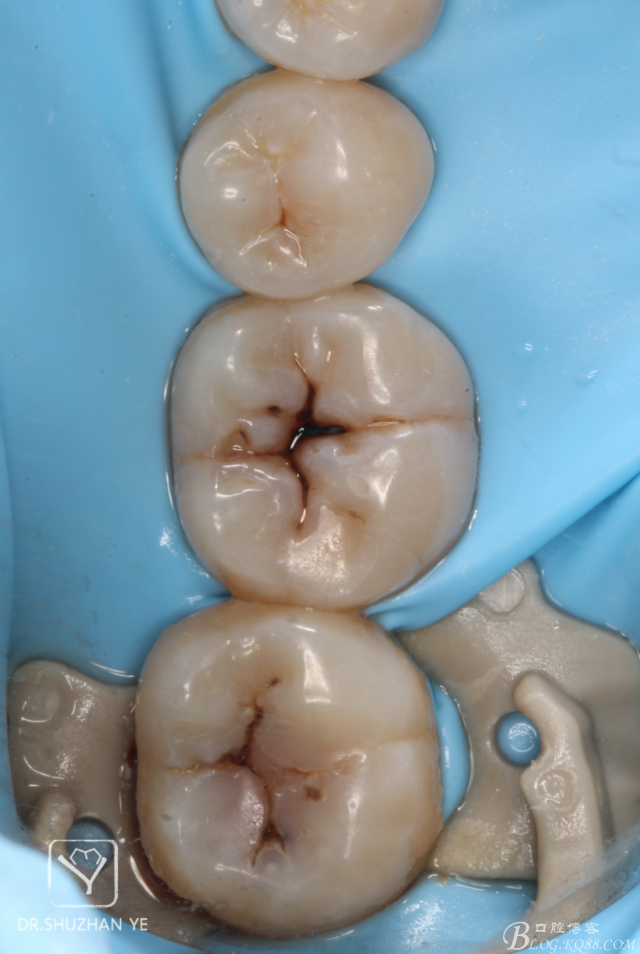

1、術(shù)前照片,46,47頜面齲壞,且頜面完整,無缺損

3、上橡皮障